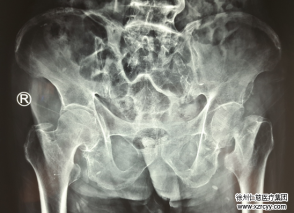

近日,betway在线登陆关节外科蒋守海主任团队顺利完成微创比基尼(DAA*Bikini)髋关节置换术。此项微创技术标志着sararz关节外科...

病例 |sararz智慧关节外科 | 疼了20年的“老大难”髋,置换手术

病例 |骑车摔倒至股骨颈骨折,Mako机器人精准置换完成髋关节